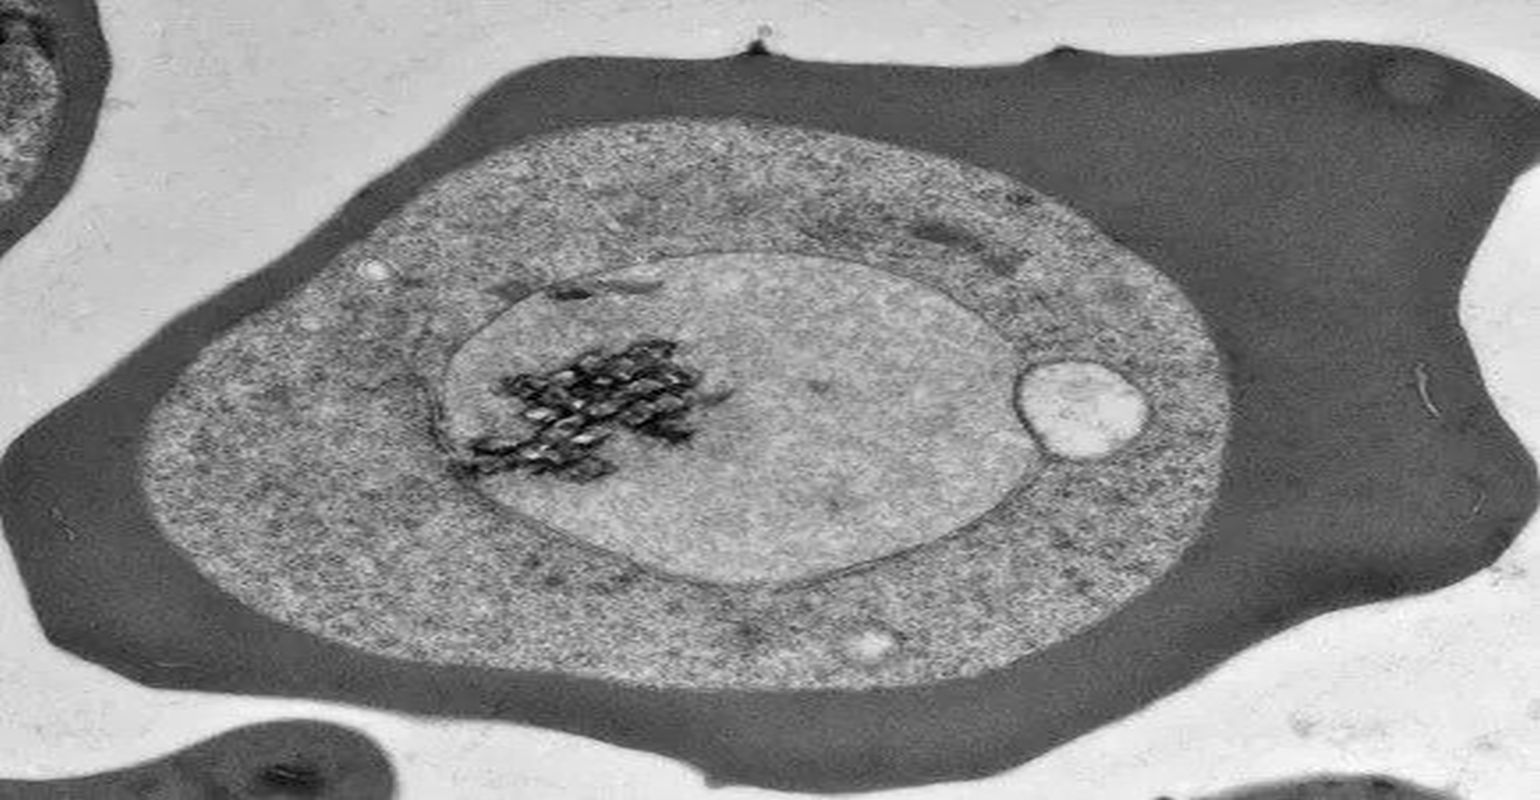

The protozoa that cause malaria enter the human body via the bite of an infected mosquito. The parasites initially develop in liver cells before moving into a host’s red blood cells, which is when the symptoms of the disease arise. The parasites are covered in a vacuolar membrane through which they must pass proteins in order to make changes to the red blood cell that allow them to survive and avoid the host immune response. Beck’s research helped to map the mechanism by which the parasites transfer the proteins and other molecules through the membrane.

To pass through the membrane the proteins must be unfolded and then threaded through a small channel, like unwinding a ball of string to pass it through the eye of a needle. This process is performed by the Plasmodium translocon of exported proteins, or PTEX for short, which is a molecular machine complex composed of three parasite proteins, Beck said. One of these proteins does the unfolding while another forms the channel. The third component connects the other two.